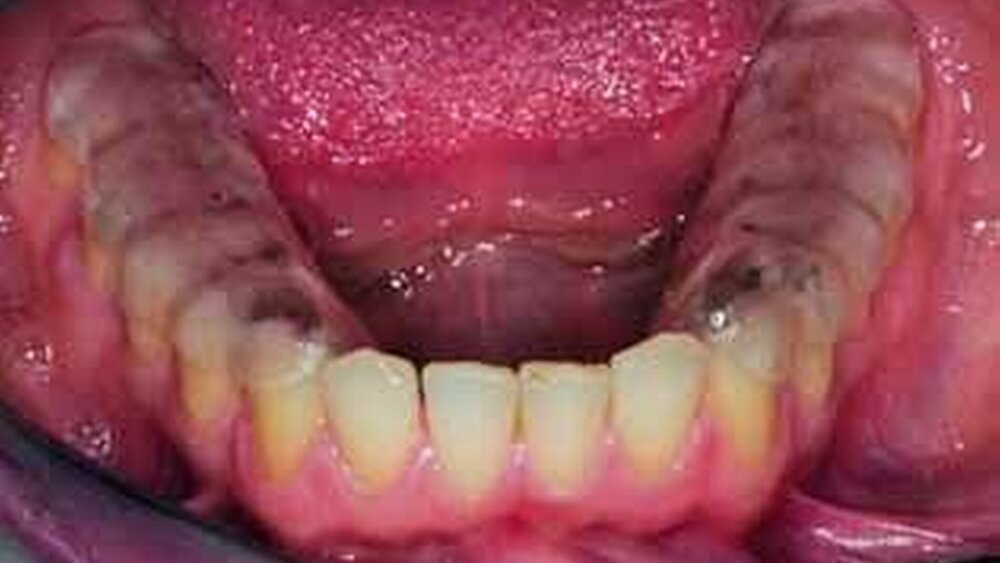

Die Äquilibrierungsschiene unterliegt dem Prinzip, die bestehende Okklusion aufzuheben und über die Schiene ideale okklusale Beziehungen herzustellen. Dadurch wird der Trigger für eine dysfunktionelle Erkrankung ausgeschaltet und während der weiteren Therapie erkannt und beseitigt. Letztendlich soll durch Einstellung einer neuen habituellen Interkuspidation eine Harmonisierung des Systems herbeigeführt werden. Die Äquilibrierungsschiene ist deshalb indiziert bei okklusions- oder parafunktionell bedingten Dento- (Okklusio-), Myo- und Arthropathien. Bei parafunktionell verursachten Dysfunktionen kann sie als Langzeitschiene (Knirscherschiene) Verwendung finden, um die Auswirkungen der Parafunktion auf die kraniomandibulären Strukturen (Zahn, Parodontium, Muskulatur und Kiefergelenk) zu mildern. Besonders dann, wenn es therapeutisch mit andere Therapiestrategien nicht gelingt, die Parafunktion zu beherrschen. Bei Arthropathien und Myoarthropathien ist die Äquilibrierungsschiene dann indiziert, wenn Stellungs- und Belastungsänderungen in den Kiefergelenken vorliegen. Symptomatisch sind sie auch bei Strukturveränderung und intrakapsulären Verlagerungen (Diskusverlagerung) anwendbar, besitzen dann aber keine kausale Wirkung. Ziel der Behandlung mit einer Äquilibrierungsschiene ist eine Harmonisierung von Muskel- und Gelenkfunktion über eine Idealisierung der Kontaktbeziehung der Zahnreihen zueinander [11, 12, 18, 22, 31, 36, 38, 42]. Über die Schiene soll ein allseitiger, gleichmäßiger, gleichzeitiger Kontakt aller Zähne in statischer und in dynamischer Okklusion eine Frontzahnführung mit Disklusion im Seitenzahnbereich hergestellt werden. Neuroreflektorisch sind durch die Propriorezeptoren der Parodontien der Zustand einer harmonischen, idealen Okklusion zu simulieren, die zur Muskelentspannung und damit zur Normalisierung der Muskeltätigkeit und Kiefergelenkbewegung führt. Die Äquilibrierungsschiene wird im halbindividuellen Artikulator aus Kalt-, besser aus Heißpolymerisat hergestellt. Dafür gilt es, das Oberkiefermodell nach einer arbiträren Gesichtsbogenübertragung und mit „Split cast“ im Artikulator zu fixieren. Die Zuordnung des Unterkiefermodells erfolgt durch ein zentrisches Registrat, in zentrischer Kondylenposition (ZKP) (Abbildung 6). Ziel ist es, die Diskus-Kondylus-Einheit am Übergang der Konkavität der Fossa zur Konvexität der Eminentia articularis, dem Wendepunkt [25], einzustellen. Es ist darauf zu achten, dass der Patient entspannt ist und sich leicht durch den Behandler führen lässt. Die Impressionen im Registrat müssen eine sichere Fixierung des Unterkiefermodells ermöglichen und sollten nicht zu tief sein (Abbildung 7, 8). Die Äquilibrierungsschiene wird in der Regel für den Oberkiefer angefertigt, da sie nur zeitweise oder nachts, auf jeden Fall in den Zeiten hoher parafunktioneller Tätigkeit, getragen wird. Die ästhetische Beeinträchtigung ist somit tolerierbar. Nur wenn durch bestehende Lücken (große Schaltlücken und Freiendsituationen) eine sichere Abstützung auf der Schiene nicht möglich ist, und wenn sie ganztags getragen werden soll, wird sie für den Unterkiefer angefertigt. Die Okklusionsschiene wird in Wachs entsprechend der aufgezeigten Prinzipien modelliert (Abbildung 9) und in Heißpolymerisat überführt. Gleichmäßige Kontakte der tragenden Höcker zur Schiene und eine harmonische Frontzahnführung sind im Artikulator herzustellen und im Mund des Patienten zu überprüfen (Abbildung 10, 11). Nur tiefgezogene Schienen, die als Äquilibrierungsschienen angewendet werden, werden immer in der gleichen Sitzung auf gleichmäßigen, allseitigen und gleichzeitigen Kontakt im Seitenzahngebiet eingeschliffen. Die Frontzähne sind in statischer Okklusion außer Kontakt zu stellen und übernehmen in dynamischer Okklusion die Führung des Unterkiefers mit Disklusion des Seitenzahngebietes! Das weitere Vorgehen entspricht der im Artikulator hergestellten Äquilibrierungsschiene. Äquilibrierungsschienen werden in regelmäßigen Kontrollsitzungen nach acht, 14 Tagen, anschließend nach vier Wochen nach den genannten Prinzipien kontrolliert und gegebenenfalls nachgeschliffen bis vollständige Beschwerdefreiheit erzielt wird. Auch soll die Okklusionsschiene auf Schliffflächen, die auf parafunktionelle Tätigkeit hinweisen, untersucht werden.

Eine Nonokklusion durch die vertikale Veränderung im Kiefergelenk durch die Diskusreposition ist entstanden (Abbildung 16). Daraus ergibt sich, dass eine Nachfolgetherapie angeschlossen werden muss, um wieder Zahnkontakte herzustellen und die erzielte Kiefergelenkposition durch eine stabile Höcker-Fossa-Relation zu sichern.